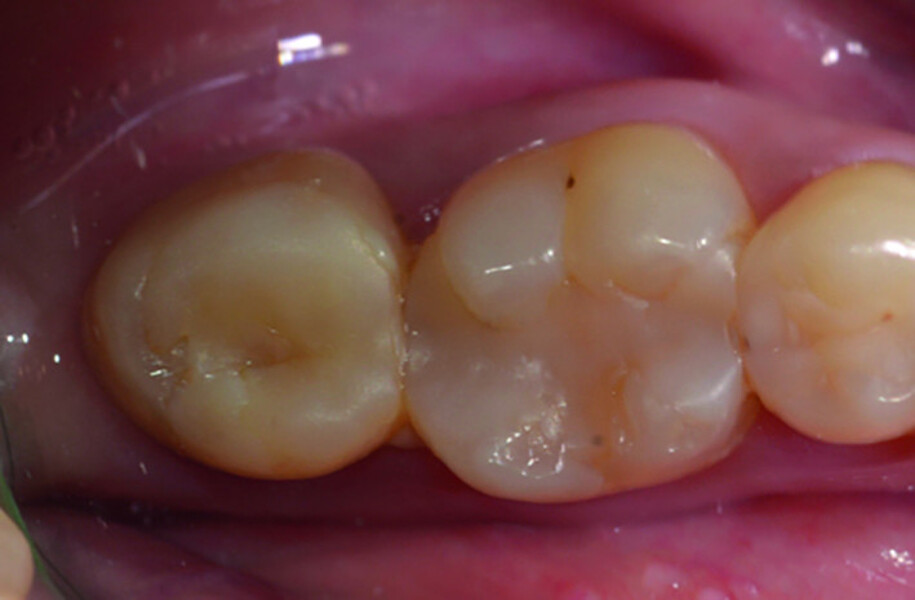

Fig. 14a: Clinical image: Pre-op.